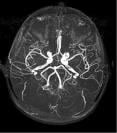

MRA of the brain.

The solution, Variable True Rate Angiography with Combined Encodings (V-TRACE), is designed to streamline MRA brain imaging by acquiring four image contrasts in one sequence, providing an imaging application for visualizing slow and fast flow vessels separately and together, as well as the brain tissue surrounding the vessels.

The V-TRACE MRA sequence enables imaging four contrasts in one sequence for greater visualization of blood vessels in the brain, particularly collateral vessels that can be difficult to see with standard MRA sequences.

V-TRACE MRA is a dual-echo 3D FE sequence in which the first echo is acquired using time-of-flight (TOF), and the second echo is acquired using flow sensitive black blood (FSBB). The sequence combines both techniques to produce MRA images that depict blood vessels with both high and low velocity. The sequence design reduces the specific absorption rate (SAR), a measurement of heat generated to the body during a MRI. The TOF data can be used to evaluate the brain parenchyma.